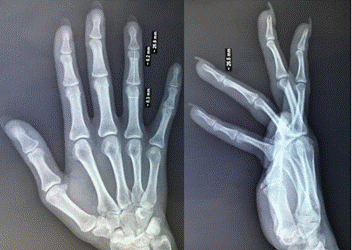

Описание клинического случая. Пациентка в возрасте 19 лет была госпитализирована в Иркутскую областную клиническую больницу в отделение микрохирургии спустя два часа после получения огнестрельного ранения. При поступлении было зафиксировано: на ладонной поверхности кисти обнаружено входное отверстие диаметром до одного сантиметра с рваными краями в области межпальцевого пространства, а также выходное отверстие диаметром до двух сантиметров. Рентгенологическое обследование показало полное разрушение средней фаланги и проксимального межфалангового сустава четвёртого пальца левой кисти, а также укорочение данного пальца (рис. 1).

Рис. 1. Рентгенограмма левой кисти до проведения первого этапа реконструктивного лечения

Источник: фото из архива автора.